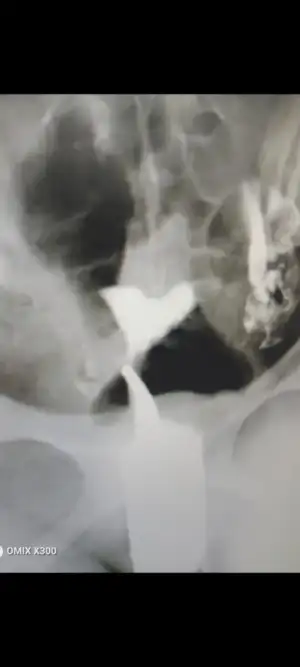

Bu şekilde benimki sizinde boylemiydi

Eklentiler

• IMG_20230618_004132_947.webp

IMG_20230618_004132_947.webp

26,2 KB · Görüntüleme: 135